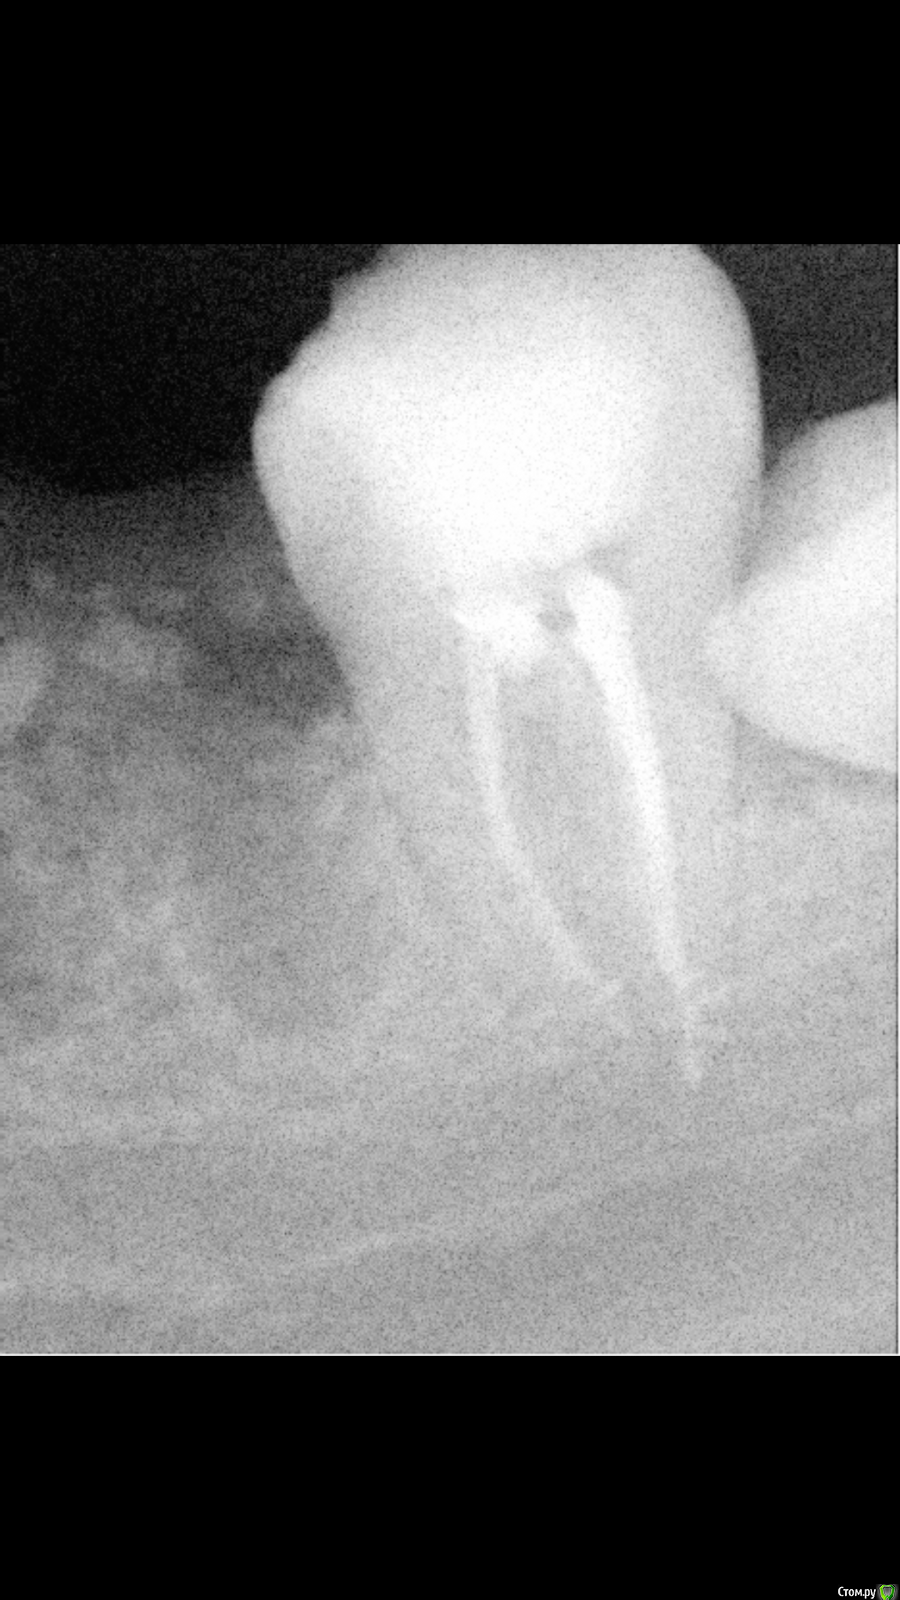

Mrs.guest Опубликовано 26 мая, 2016 Автор Поделиться Опубликовано 26 мая, 2016 Боли не от неудаленного нерва, а от травмы периодонта (то, что за пределами зуба).Травма может быть химическая (жидкости для промывания каналов, пломбировочный материал), может механическая (инструментом). Ни то, ни другое не является непоправимой ошибкой. Так иногда бывает. Содовые полоскания и обезболивающие и все придет в норму.Очень надеюсь на это,боялась, что придутся все опять разсверливать т.к боль эти 2 дня дикая. спасибо вам больше, а на снимке в принципе никаких претензий нет к пломбировке? Смущают тёмные пятна сразу над каналами или это эффект временной пломбы коронки? Ссылка на комментарий

Mrs.guest Опубликовано 27 мая, 2016 Автор Поделиться Опубликовано 27 мая, 2016 По времени дискомфорт после пломбировки может быть до нескольких недель, постепенно уменьшающийся. Но это никак не острая боль. Покажитесь лучше ещё раз доктору, может это какой-то из соседних зубов Вас беспокоит.Соседний удалён недавно, а другой зуб мудрости упирается в него конечно но на снимке ничего особенного говорят, что вряд ли он даёт такую боль, боюсь, что просто сильно перепломбировал врач каналы или как то не до конца почистила.. Ссылка на комментарий